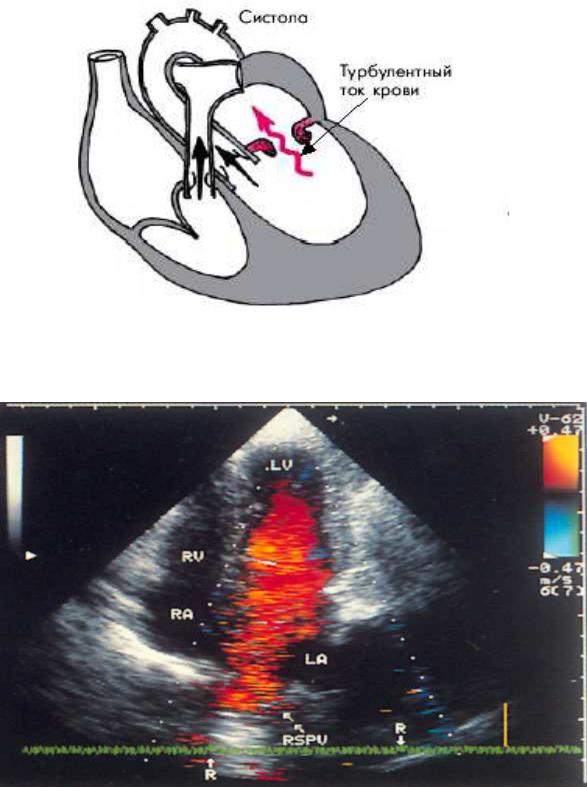

Fig.1. Mitral incompetence

Fig.2. The position of the apical four-chamber hearts: a color Dop pler study of the early diastolic filling of the left v entricle. Registers a unidirectional movement of blood in the pulmonary veins, left atriu m and left ventricle towards the apex o f the heart. LV — left